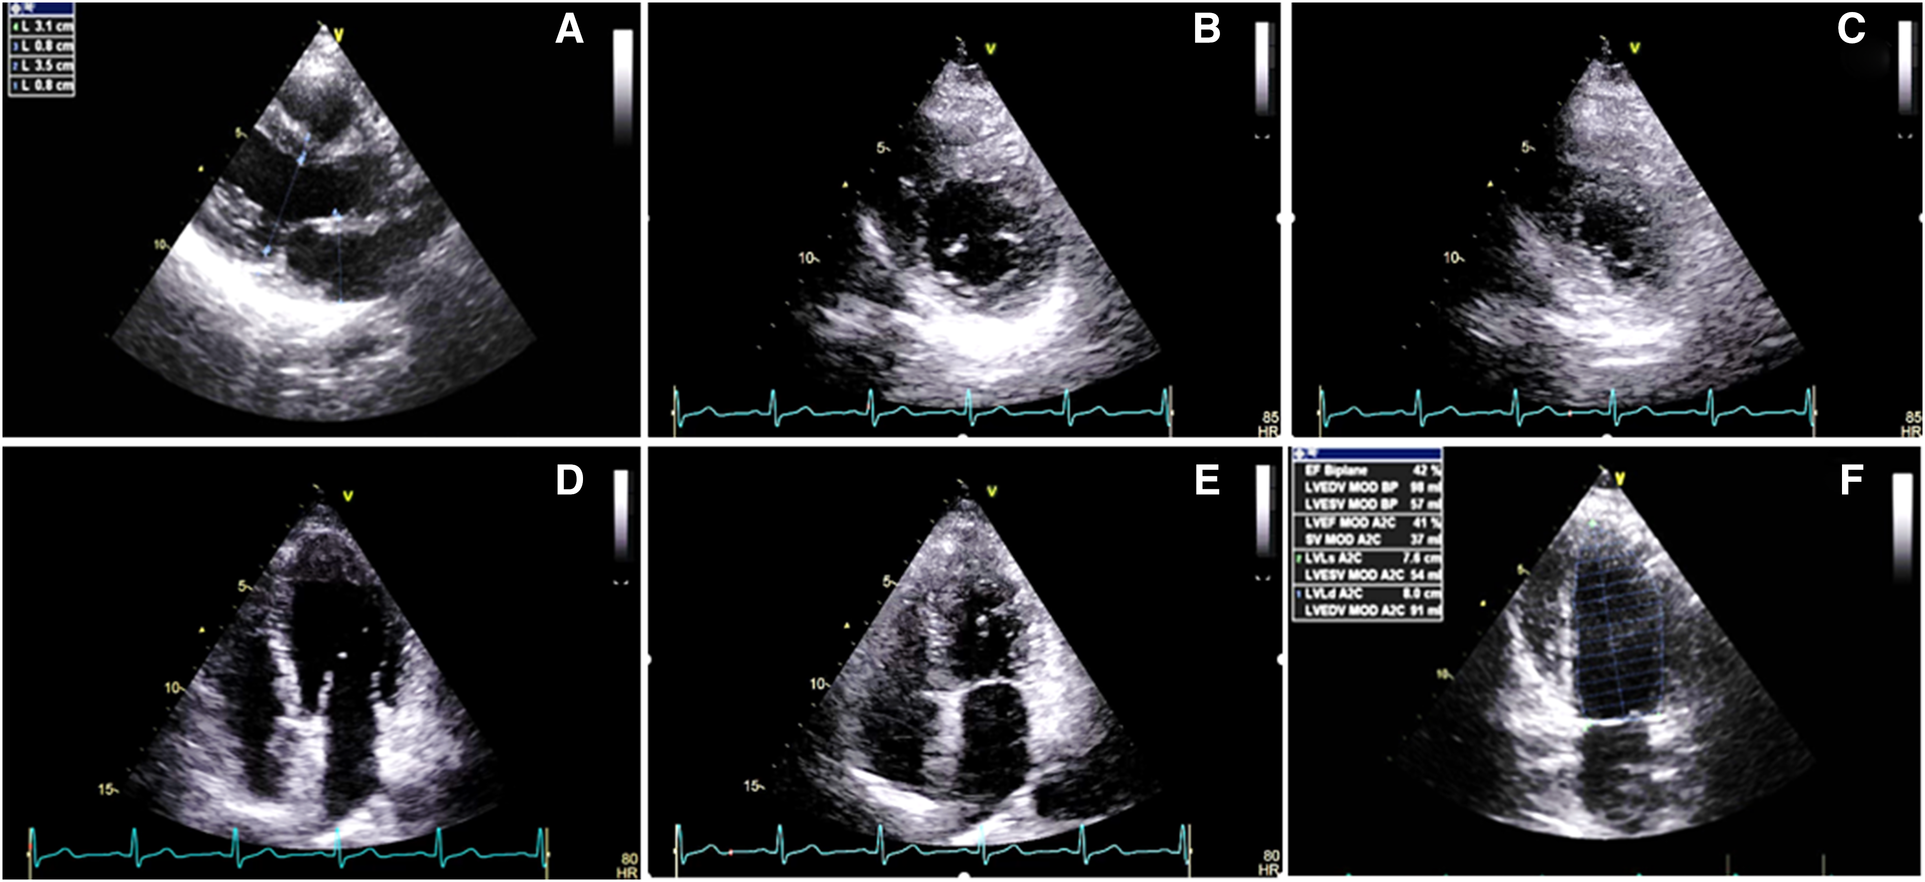

Figure 1

Two-dimensional transthoracic echocardiography 1 week before the radiotherapy course (A–F), illustrating the normal thickness of the left and right ventricular walls, in addition to global mild left ventricular systolic dysfunction: (A) PLAX view. (B) PSAX in the end-diastole. (C) PSAX in the end-systole. (D) A4C view in the end-diastole. (E) A4C view in the end-systole. (F) LV EF = 42% by Simpson's method. PLAX, parasternal long axis view; PSAX, parasternal short axis view; A4C, apical four chamber view.